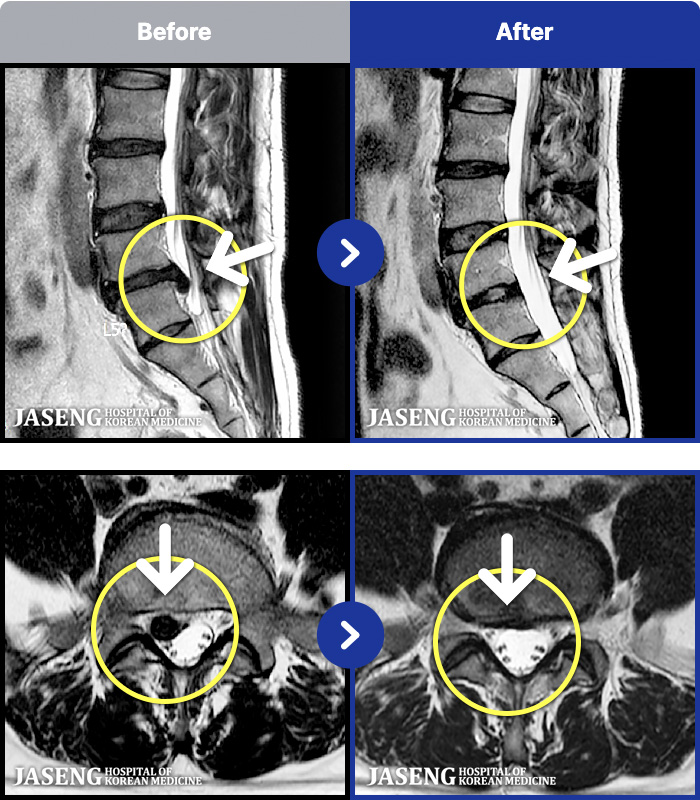

- MRI ġ

MRI ġ

181 MRI ũ ʸ Ȯϼ.